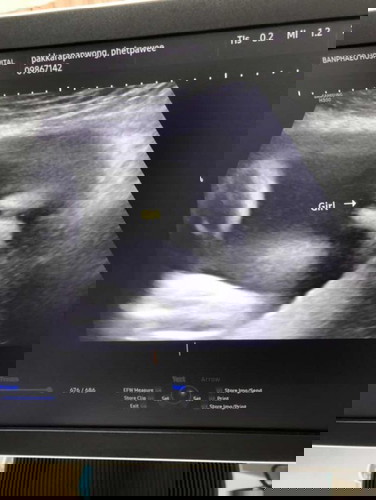

คุณแม่เดือนตุลาคมค่ะ

ท้องแหลมมากเลยค่ะแต่ซาวหมอบอกผู้หญิงคุณแม่บ้านไหนเป็นบางค่ะ

ไม่แปลกนะคะเห็นคนเขาว่าท้องแหลมผู้ชาย ท้องกลมผู้หญิง บ้านนี้ท้องกลมทั้ง3ท้อง ได้ทั้งชาย&หญิงค่ะแม่

บ้านนี้ท้องแรกกลมได้ผู้ชายท้องสองแหลมได้ผู้หญิงจร้า